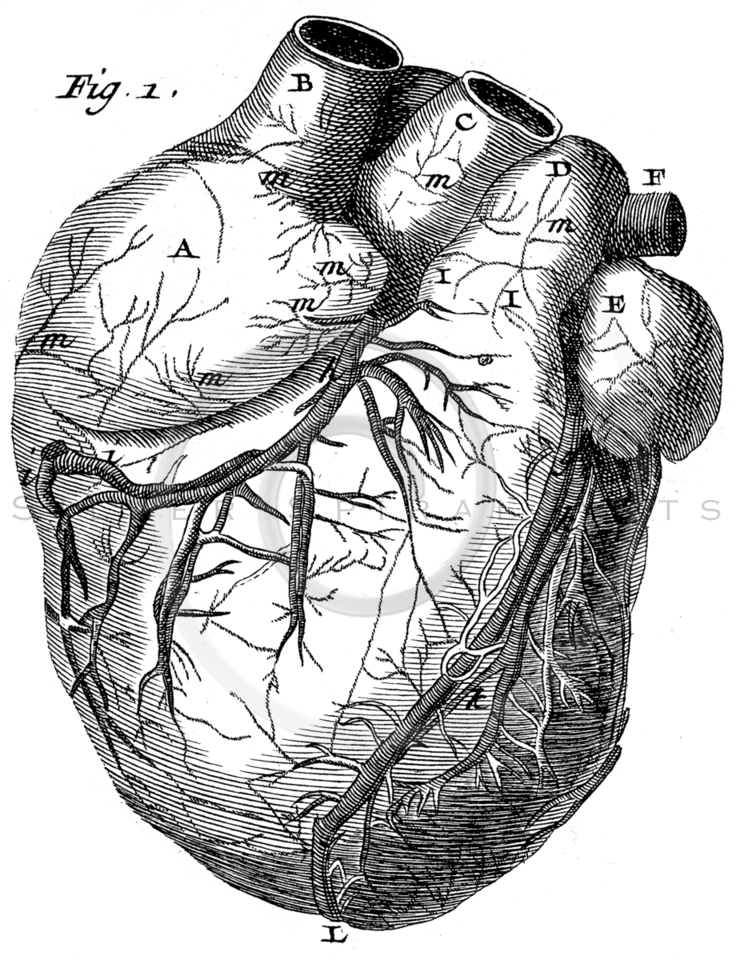

976x976 Vintage Heart Anatomy Illustration Printable 1800s Antique

338x450 Anatomy Of The Heart Vintage Art Prints, Vintage Art And Giclee

473x640 Image Result For Vintage Anatomical Heart Diagram Sketch

1079x1300 Drawing A Human Heart Anatomical Human Heart. Engraved Detailed

736x960 Royalty Free Stock Vintage Illustrations Photo Keywords Body, Anatomy

542x800 Vintage Heart Anatomy Stickers By Stilleskygger Redbubble

722x900 Heart Anatomy, 18th Century Photograph By